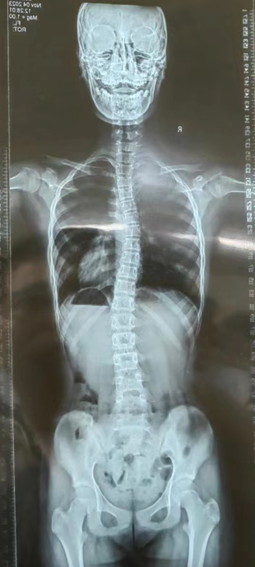

案例三

2023年8月

2023年11月